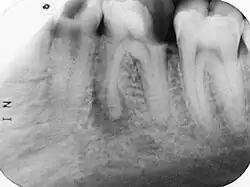

Wenn die primär chronische Form in eine akute Entzündung umschlägt, tritt ein typischer Klopfschmerz auf. Röntgenologisch sind apikale Aufhellungen meist erst nach mehrwöchigem Krankheitsverlauf zu erkennen. Als erstes Anzeichen ist ein erweiterter Periodontalspalt sichtbar. Veränderungen der Knochendichte sind im Röntgenbild erst erkennbar, wenn mindestens 30 % des Mineralgehaltes des Knochens abgebaut sind. Das kann bei einer apikalen Ostitis einige Tage bis Wochen dauern. Bei geringen Beschwerden und unsicherer Aussagekraft des Röntgenbildes ist eine Wiederholungsaufnahme erst nach drei Monaten angebracht.

Um die Auswertung endodontischer Zahnfilme zu erleichtern und die Bewertung des Zustands der Periapikalregion zu vereinfachen und nach Möglichkeit zu standardisieren, wurden verschiedene Indizes entwickelt, unter anderem von Reit und Gröndahl der Periapical Probability Index (PRI)[2] oder von Ørstavik der Periapikalindex (PAI).[3]

Differentialdiagnose: apikales Granulom oder radikuläre Zyste; Zustand nach Wurzelbehandlung; Vorwölbung der apikalen Aufhellung in die Kieferhöhle

Die Unterscheidung einer apikalen Periodontitis von einer dentogenen Zyste (radikuläre Zyste) ist nur histologisch möglich. Die ältere Lehrmeinung, dass röntgenologische Aufhellungen über 7 mm Durchmesser eher für eine Zyste sprechen, wurde verworfen. Ebenso, dass ein scharf abgegrenzter Rand im Röntgenbild eher für eine Zyste spricht.